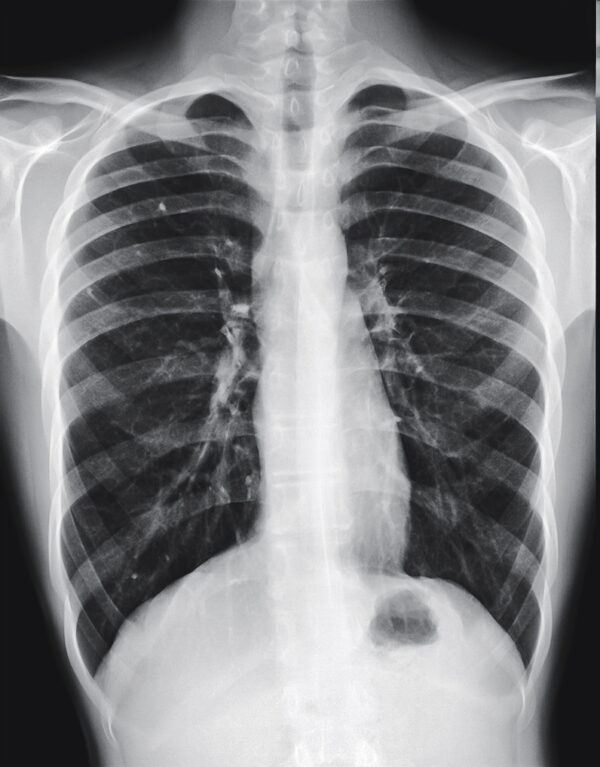

Pectus Carinatum

Pectus carinatum is a deformity of the chest in which the breastbone protrudes outwards. The bulging gives the chest a birdlike appearance which is why the condition is sometimes referred to as pigeon chest. It occurs when the cartilage that holds the ribs to the breastbone has a defect, and the cartilage pushes the breastbone and ribs outwards causing the chest to jut outwards. It is unknown what causes this chest deformity, but is believed to be genetic in nature.

While the condition is categorised by the protrusion of the breastbone forwards, pectus carinatum is often only developed during early adolescence when the growth spurt hits. It is then that the symptoms worsen and the physical deformity begins to show.